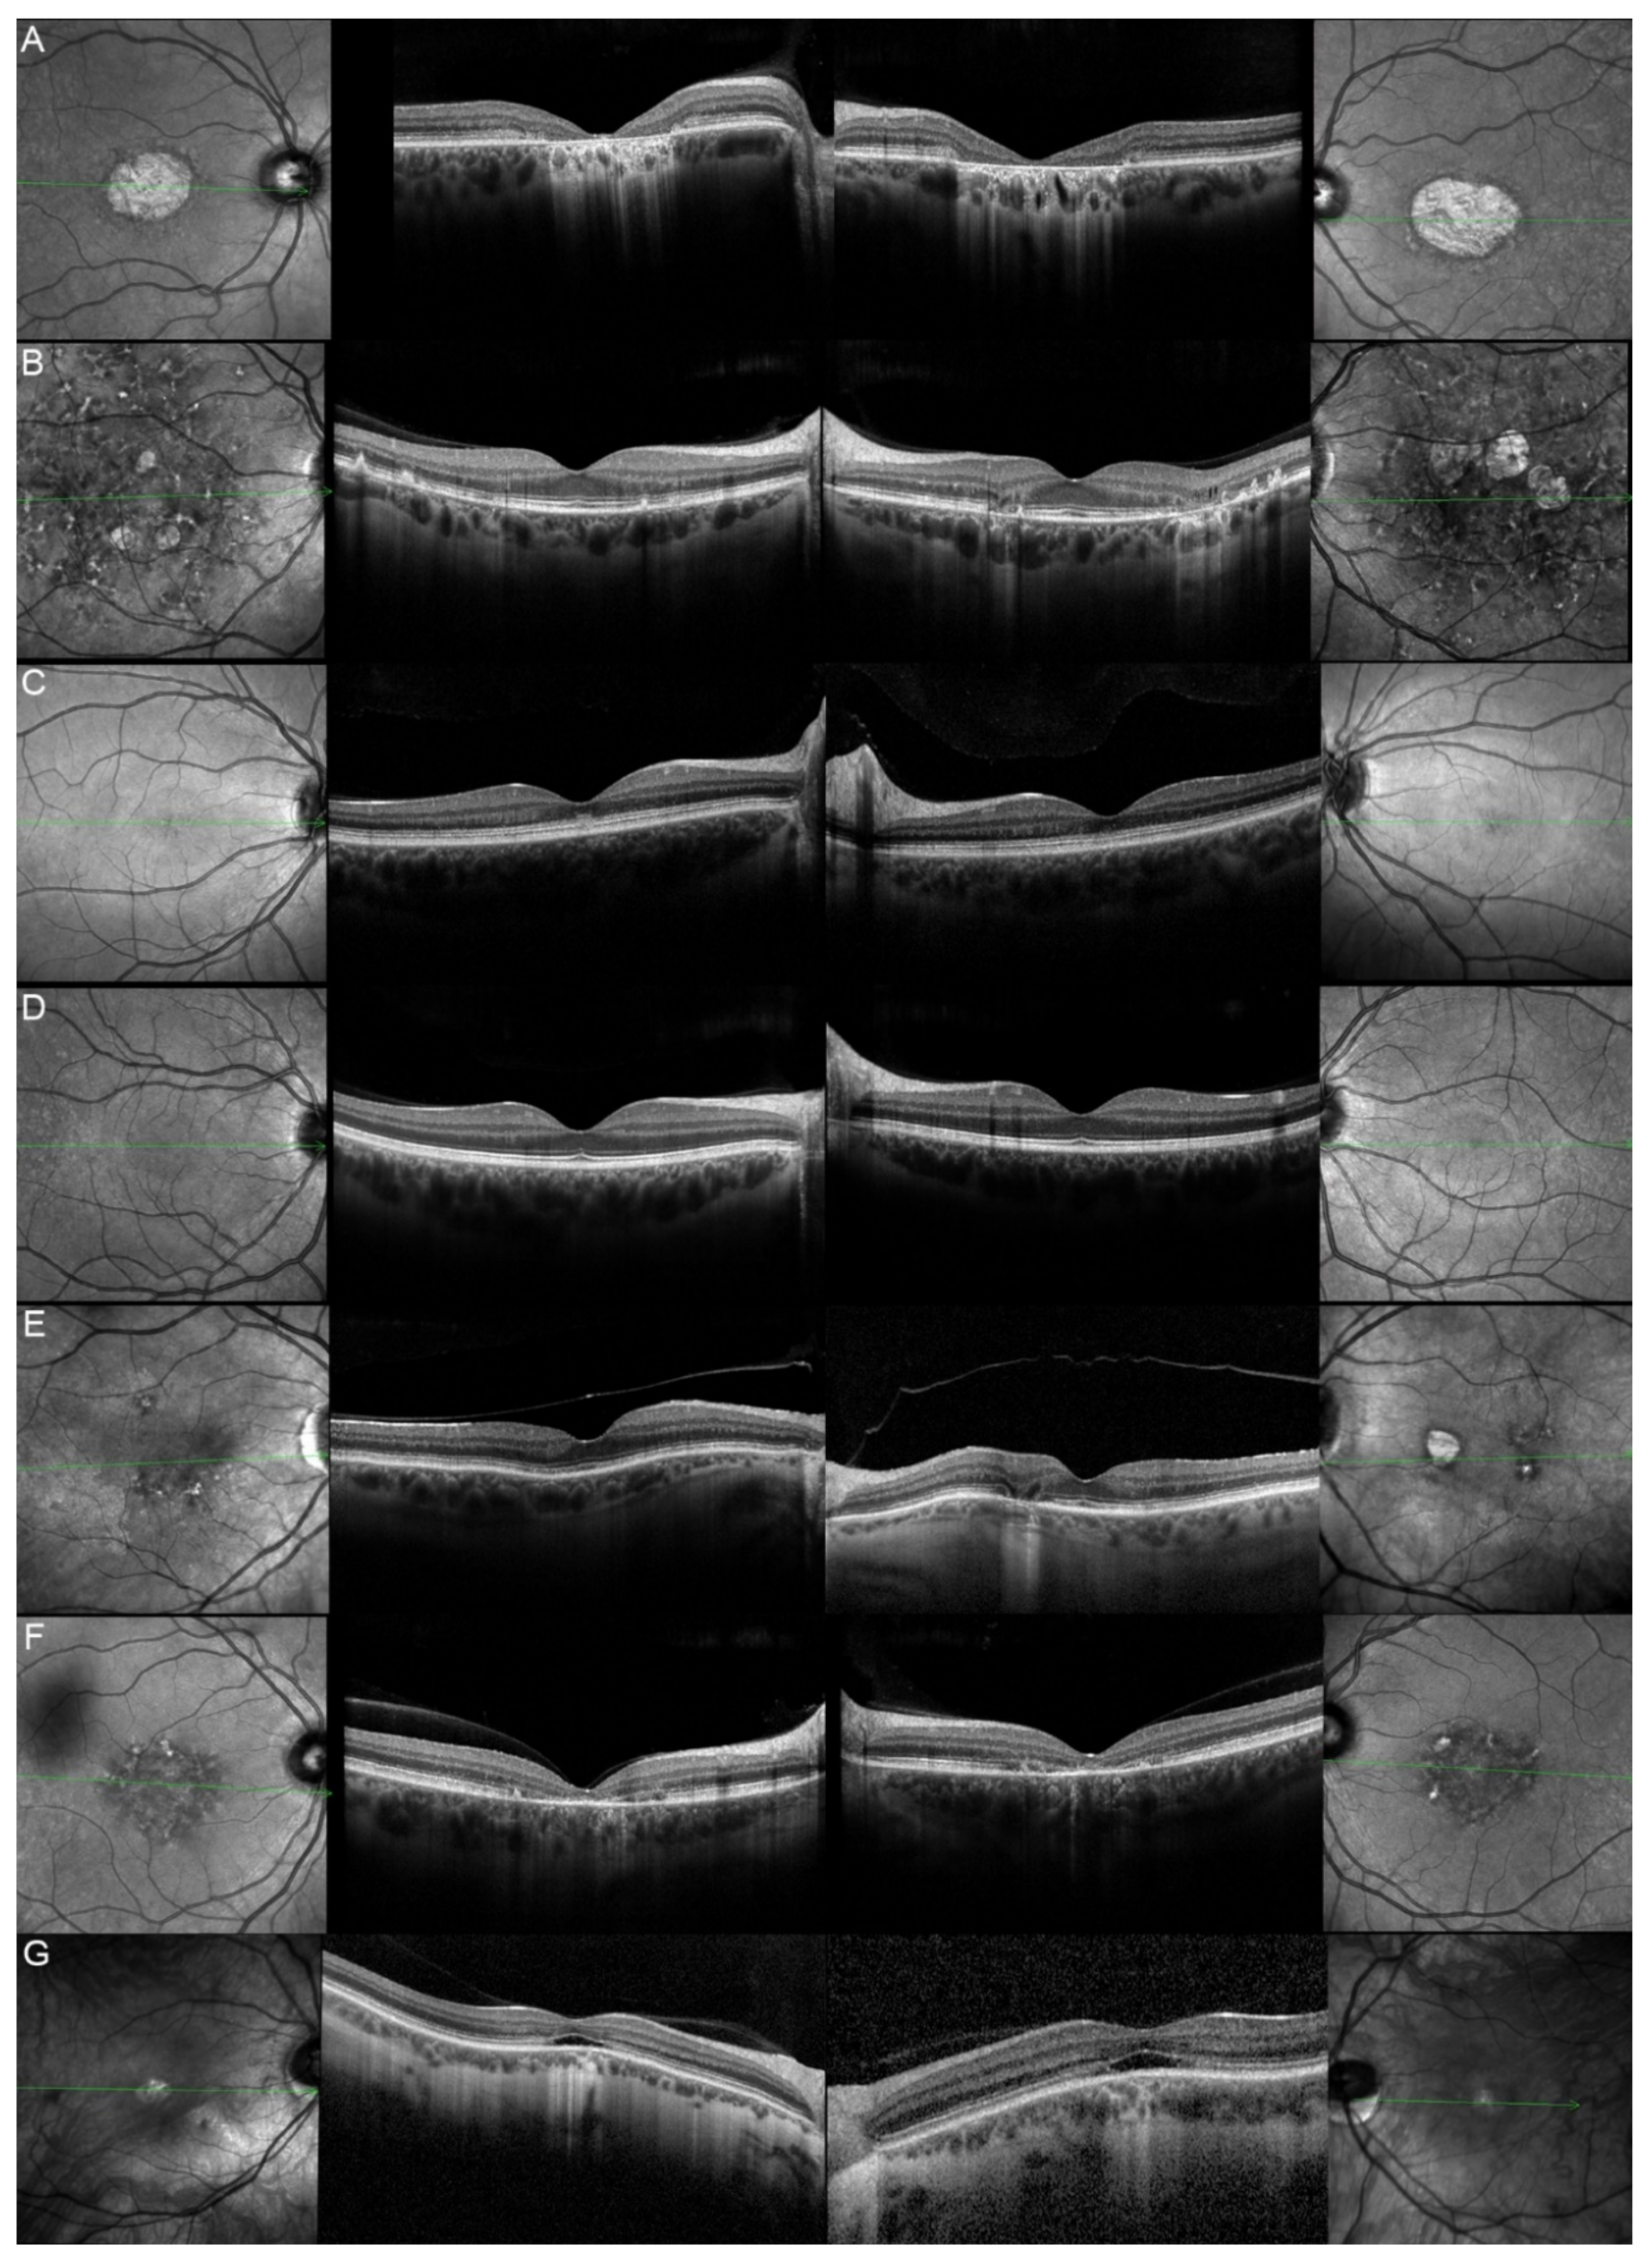

| Patient | Gene | Age | Sex | FAF | OCT |

|---|---|---|---|---|---|

| 1, II.2 | ABCA4 | 53 | F | Foveal HPAF | Subretinal hyperreflective deposits |

| 2, II.1 | ABCA4 | 18 | F | Central HOAF; concentric ring of HPAF | Central EZ disruption with gap; ONL atrophy |

| 3, II.2 | ABCA4 | 18 | F | Foveal HOAF; central mottled pattern of HPAF and HOAF flecks | Central EZ loss; central ONL atrophy |

| 4, II.2 | ABCA4 | 27 | F | Foveal HPAF; parafoveal HOAF; paramacular HPAF | Central EZ loss; central ONL atrophy |

| 5, II.2 | ABCA4 | 69 | F | Mid-peripheral mottled HOAF | Mid-peripheral ONL atrophy, lamellar macular hole (OD) |

| 6, II.2 | ABCA4 | 53 | F | Foveal HOAF; central mottled pattern of HPAF and HOAF flecks | Central EZ disruption with gap (OS) and loss (OD); central ONL atrophy |

| 7, II.1 | ABCA4 | 19 | F | Central HOAF; HPAF flecks | Central EZ loss; central ONL atrophy |

| 8, III.2 | ABCA4 | 30 | M | Central HOAF; HPAF flecks | NA |

| 9, II.2 | ABCA4 | 44 | F | Central mottled pattern of HPAF and HOAF flecks | Central EZ loss; central ONL atrophy |

| 10, I.2 | ABCA4 | 51 | F | Foveal HOAF; central mottled pattern of HPAF and HOAF flecks | Perifoveal EZ loss; perifoveal ONL atrophy; loss of the foveal depression |

| 11, III.1 | ABCA4 | 53 | M | Extended central and peripheral HOAF; panretinal diffuse mottled pattern of HPAF and HOAF flecks | ONL atrophy; peripheral choroidal atrophy; RPE atrophy; subretinal hyperreflective deposits |

| 12, II.2 | ELOVL4 | 37 | F | Central HOAF; concentric ring of HPAF | Central EZ loss; central ONL atrophy and RPE atrophy |

| 13, II.1 | ELOVL4 | 46 | F | Multifocal areolar parafoveal HOAF; mottled pattern of HPAF and HOAF flecks; perimacular to mid-peripheral HPAF flecks | Perimacular EZ loss; perimacular ONL atrophy; subretinal hyperreflective deposits |

| 13, III.2 | ELOVL4 | 19 | F | No special features | Subfoveal hyperreflective deposits (OD) |

| 13, III.1 | ELOVL4 | 21 | M | NA | No special features |

| 13, I.1 | ELOVL4 | 82 | M | Areolar HOAF; paracentral mottled pattern of HPAF and HOAF flecks | ONL thinning; perimacular localised EZ loss (OS) |

| 14, II.4 | ELOVL4 | 48 | M | Central mottled pattern of HPAF and HOAF flecks | Central EZ loss; central ONL atrophy; perimacular subretinal hyperreflective deposits |

| 15, II.3 | ELOVL4 | 34 | M | Subfoveal HOAF; concentric ring of HPAF | Central EZ disruption with gap; central ONL atrophy |

| 16, III.2 | ELOVL4 | 28 | F | NA | NA |

| 17, II.1 | PRPH2 | 51 | F | Butterfly pattern of HPAF and HOAF flecks; paramacular to mid-peripheral HPAF flecks | Irregular EZ thickening |

| 18, II.2 | PRPH2 | 69 | M | Subfoveal HOAF (OS); butterfly pattern of HPAF and HOAF flecks; paramacular to mid-peripheral HPAF flecks | Central EZ loss (OS); central ONL atrophy (OS); localised ONL thinning (OD) |

| 19, III.2 | PRPH2 | 39 | F | Central areolar HOAF; disseminated nummular HPAF | Extended retinal atrophy |